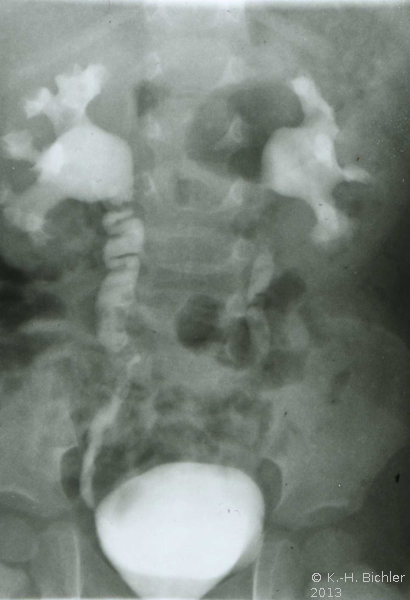

Als Beispiel die Ureterabgangsstenose bei multiplen Nierenbeckenkelchsteinen eines 2 Jahre alten Jungen (Abbildung HG2).